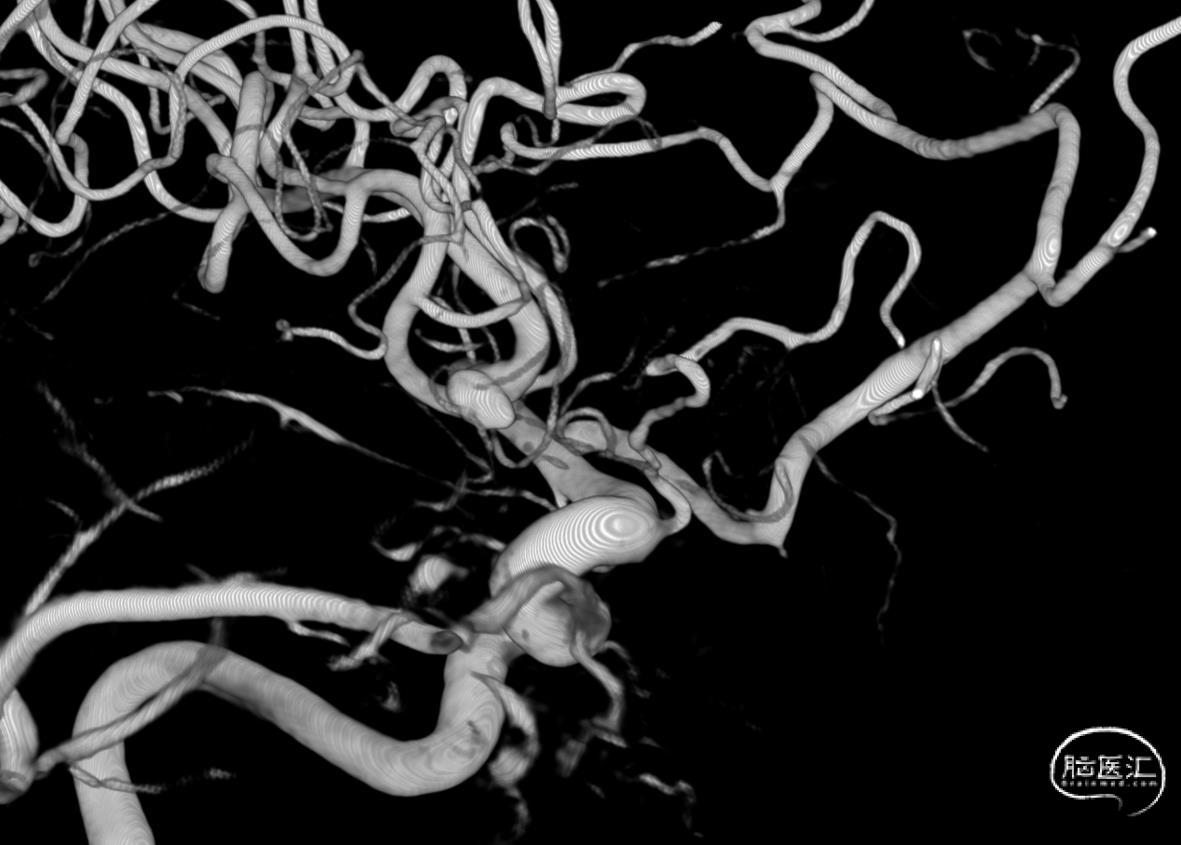

3D-RA成像

动脉瘤位于M1分叉处,三分支。